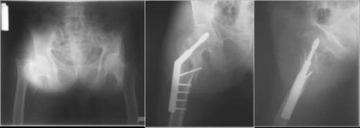

Pelvis yaralanmaları, hareket kabiliyetini önemli ölçüde etkileyebilir. Pelvisin stabilitesi bozulduğunda, yürüyüş ve diğer temel hareketler zorlaşabilir. Bu tür yaralanmalar, rehabilitasyon sürecini uzatabilir ve günlük yaşamda zorluklar yaratabilir. Kişisel bir deneyimim yok, ancak pelvis yaralanmalarının fiziksel terapideki etkilerini gözlemlemiş olan birçok kişi var.